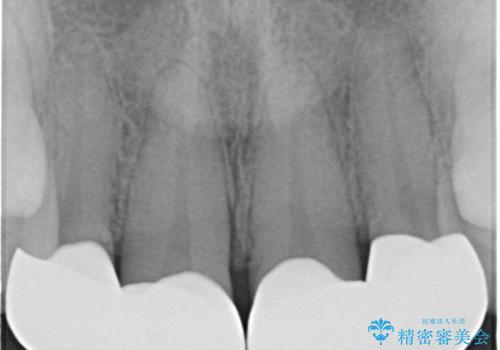

虫歯になっている歯はないので、患者様としっかり相談をして被せ物治療をする事に致しました。

適合の良い被せ物が入りました。

樹脂の素材とは違い、セラミックやジルコニアの素材の被せ物は劣化をしません。また、虫歯の再発リスクも低くなります。